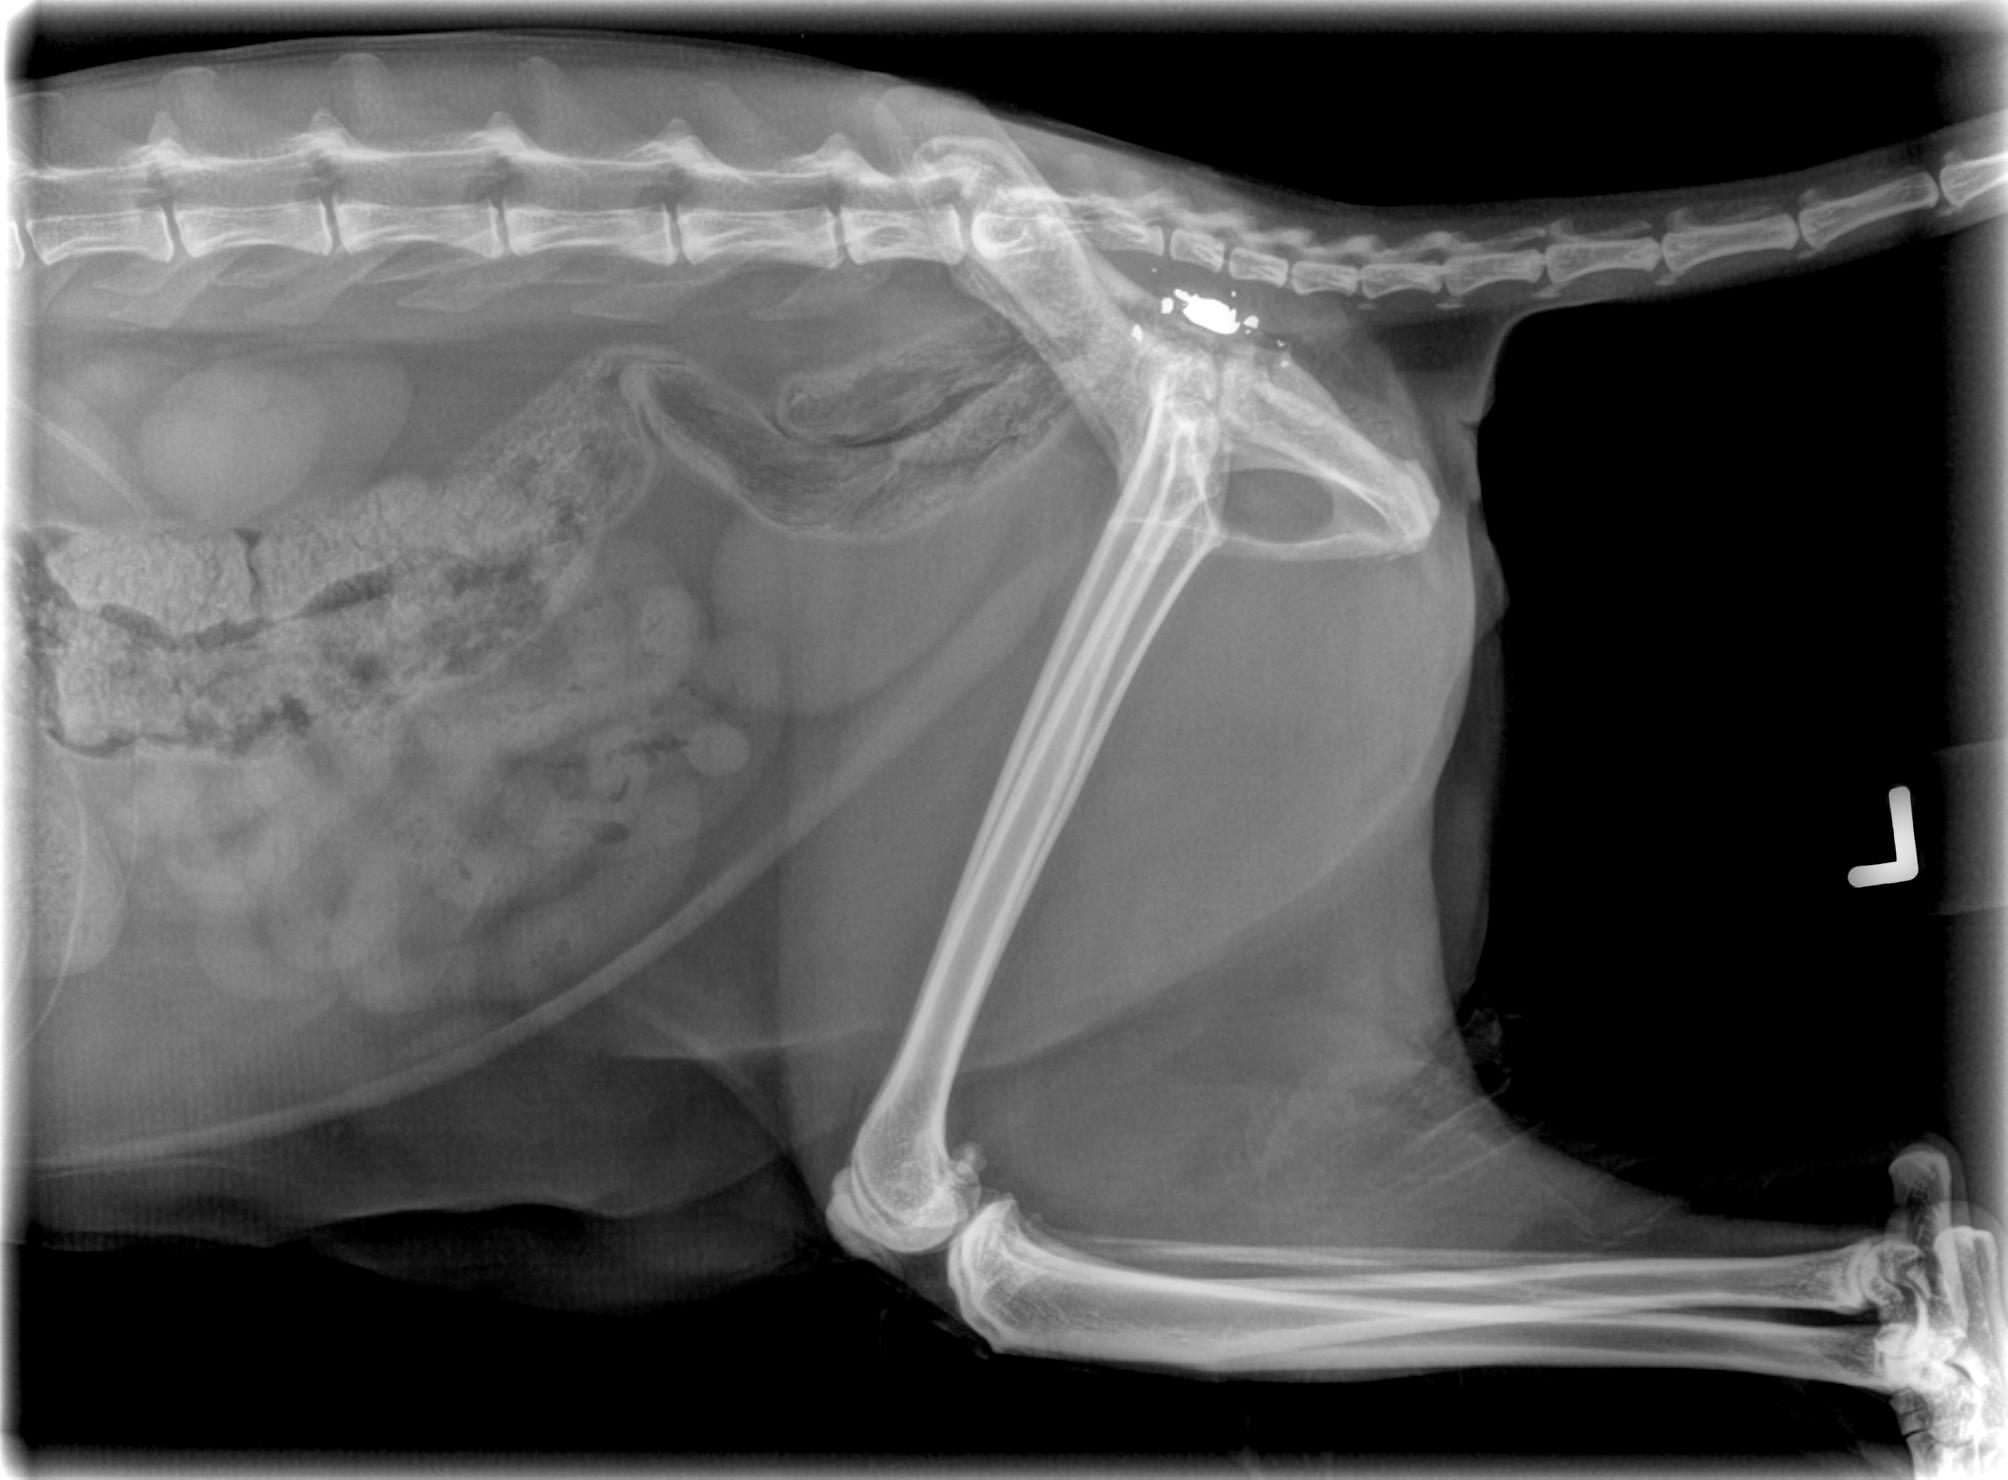

Pelvis cracked by impact of round, and you can see where some of it is way too close to the spinal column to go digging around.

If she doesn’t recover use of her leg at all, they will operate…she goes back in two weeks and must keep cone on, as patch is apparently some wicked awesome stuff and if she licks it, she can OD.